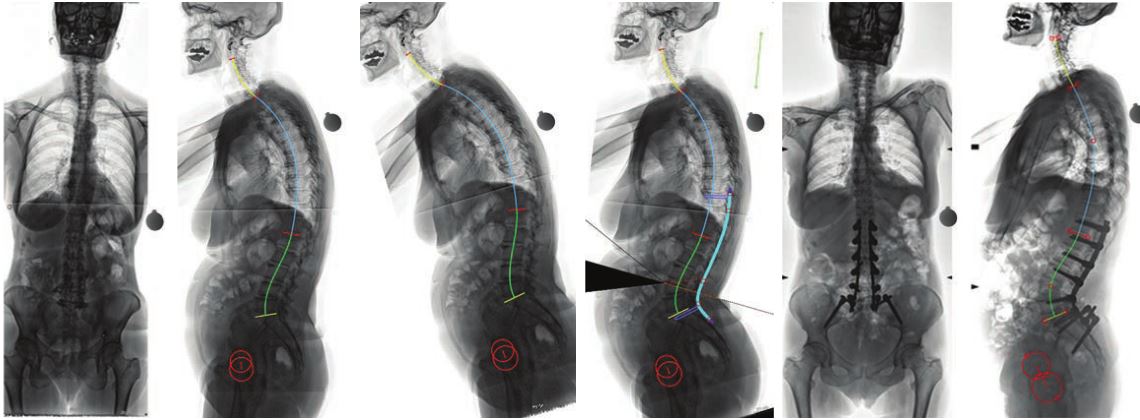

Η αντιμετώπιση των παραμορφώσεων της σπονδυλικής στήλης των ενηλίκων, ένα πολύ ιδιαίτερο και δύσκολο χειρουργικό πρόβλημα, βασίζεται πλέον στον ακριβή γεωμετρικό τρισδιάστατο προεγχειρητικό σχεδιασμό, με τη βοήθεια υπολογιστικών προγραμμάτων χειρουργικού σχεδιασμού. Με την τεχνική αυτή, σχεδιάζεται με απόλυτη ακρίβεια η χειρουργική επέμβαση, ενώ προκατασκευάζονται και υπάρχουν διαθέσιμα στο χειρουργείο εξατομικευμένα, για τον κάθε διαφορετικό ασθενή, υλικά σπονδυλοδεσίας.

Επιπλέον, με την χρήση της διεγχειρητικής τρισδιάστατης νευροπλοήγησης (ρομποτική χειρουργική της σπονδυλική στήλης), είναι εφικτή η ταχύτατη, με ακρίβεια και ασφάλεια, εμφύτευση των υλικών οστεοσύνθεσης και η πραγματοποίηση ακόμη και των πιο λεπτών χειρουργικών επεμβάσεων, σε όλες τις περιοχές της σπονδυλικής στήλης, από τον αυχένα έως και το ιερό οστό. Η διόρθωση της παραμόρφωσης ελέγχεται διεγχειρητικά και ο χειρουργός έχει τη δυνατότητα επιπλέον τροποποιήσεων την ώρα του χειρουργείου, ώστε να πετύχει το καλύτερο δυνατό αποτέλεσμα.